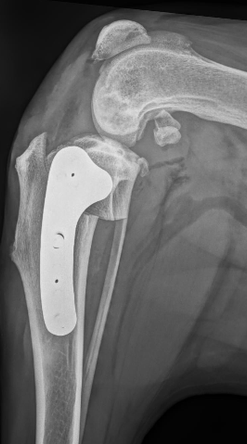

The TPLO procedure itself involves the use of a curved saw blade to make a curved cut on the inside of the tibia. The cut portion is rotated into the correct angle and a stainless steel bone plate is placed to hold the two pieces of the tibia into alignment.

The X-ray to the left was taken immediately after surgery to check implant positioning.